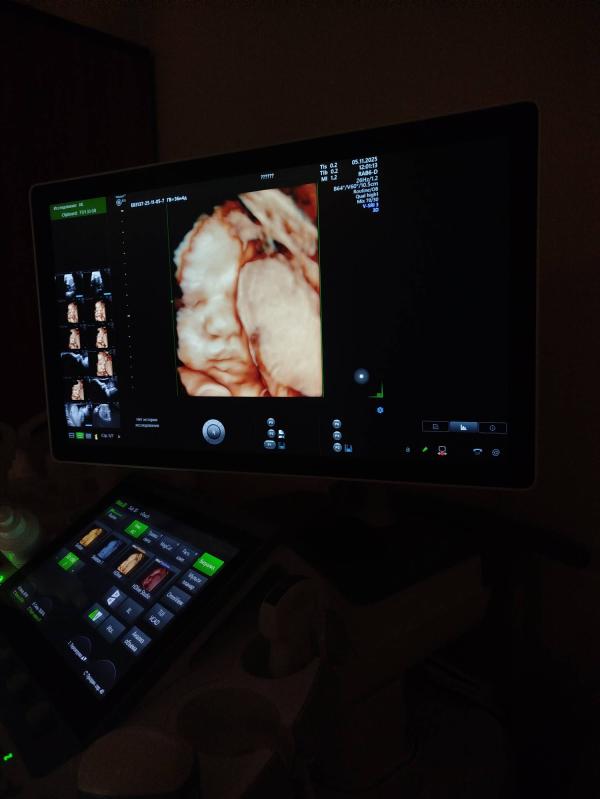

Люди делают новых людей🤭

Так же ставят зрп и маловесный плод, но посмотрите на эту бусинку😍

Через 5 дней прием в жк и там решим что делать дальше. Головка прижата, но шейка длинная еще. Ходим🥸 кровотоки в идеале, в целом все хорошо, кроме ог и ож

Бусинка🥰

Какая кнопочка красивая🥰 ттт на Вас

О, эта дама с трудом далась посмотреть 🤪 сказали в следующий раз прийти на фотометрию если надо будет

Это мое первое УЗИ в 3д, я и не думала, что сделает, потому что шла на обычное😅